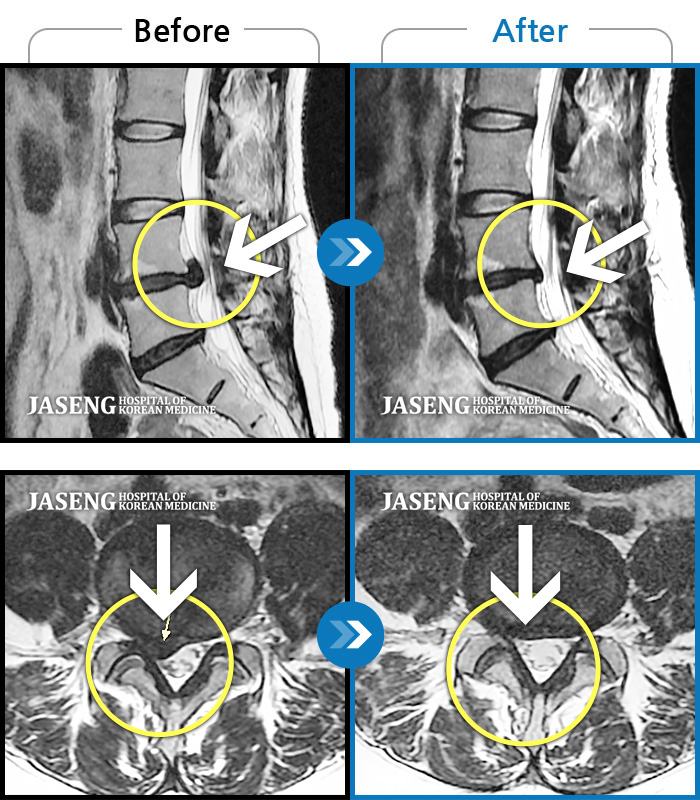

허리디스크

목동 · 이민수 원장

오른쪽 정강이 감각이 무디고, 발바닥 통증

촬영시기

2019.07.16 ~ 2020.02.13

2020.02.21